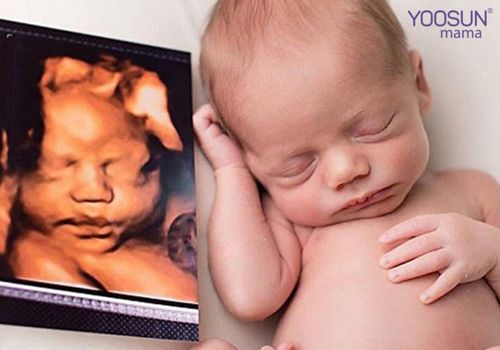

Thông qua màn hình máy tính cha mẹ, bác sĩ sẽ thấy được những cử chỉ của thai nhi như: Giơ tay, đạp chân, xoay mình, ngáp ngủ… Một số trường hợp siêu âm còn thấy em bé đang mút tay…

Hình ảnh siêu âm thai 4D

Đặc biệt, với những hình ảnh mà kỹ thuật siêu âm này thu được bạn có thể lưu lại dưới dạng đĩa DVD, VCD. So với các kỹ thuật siêu âm thông thường, siêu âm thai 4D được xem là bước tiến hiện đại và vượt bậc.

Thay vì những tấm hình đen trắng như công nghệ siêu âm 2D giờ đây máy siêu âm 4D cho hình ảnh, video chất lượng rõ nét và chân thực.